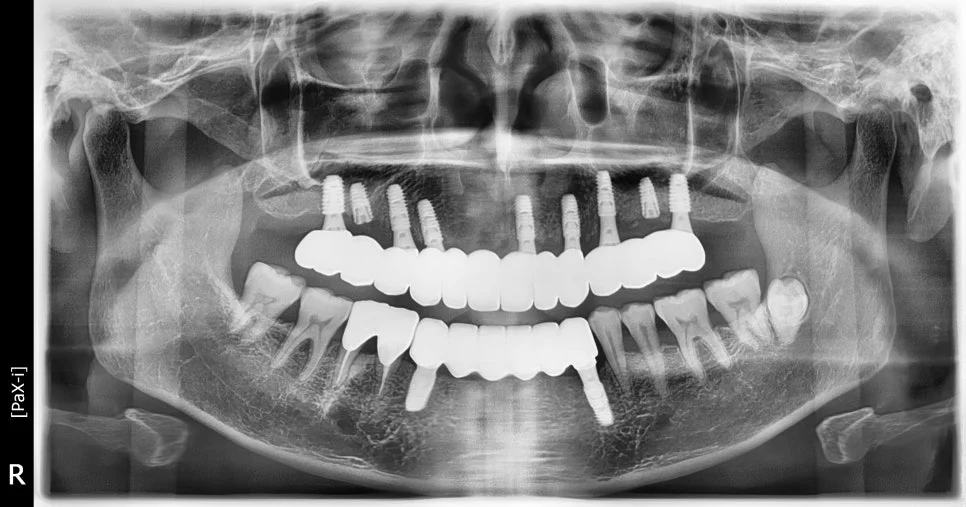

수술 전후 파노라마 비교

CBCT 단면 – 각 임플란트 개별 검증

CT 상에서 하얀색인 임플란트가 1. 온전히 뼈 안에 잠기게(1~2mm 깊게) 그리고 2. 가급적이면 입천장 쪽으로 식립되었다면 잘 심긴 임플란트입니다. (입술 쪽 뼈는 쉽게 흡수됩니다ㅜ)